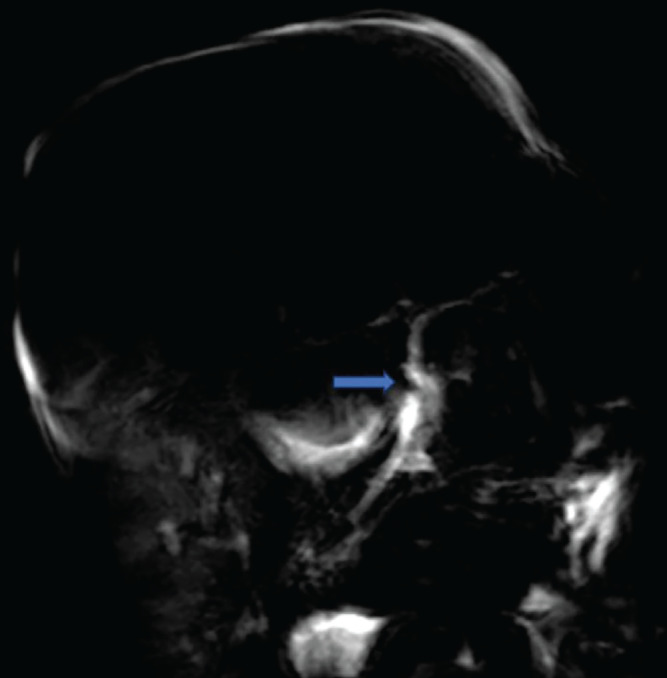

Endoscopic biliary stenting is a widely adopted technique for managing bile duct injuries post-cholecystectomy. However, its complications can have severe consequences. Although rare compared to other endoscopic retrograde cholangiopancreatography-related complications, duodenal perforation due to stent migration carries a significant risk of morbidity and mortality. While biliary stenting is often considered a less invasive alternative to surgery, timely recognition and management of potential complications remain crucial. We present a case of duodenal perforation due to biliary stent migration in a 49-year-old woman following laparoscopic cholecystectomy, emphasizing the effectiveness of conservative management, including the key role of interventional radiology, in selected patients.

Abstract Image